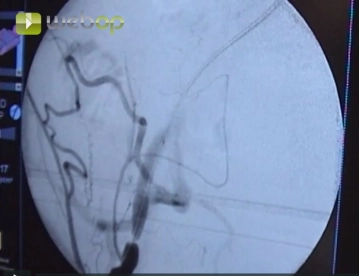

Punción de la arteria femoral común en dirección a la arteria ilíaca externa. Introducción de una vaina 6F según Seldinger. Avance del alambre guía bajo control fluoroscópico.